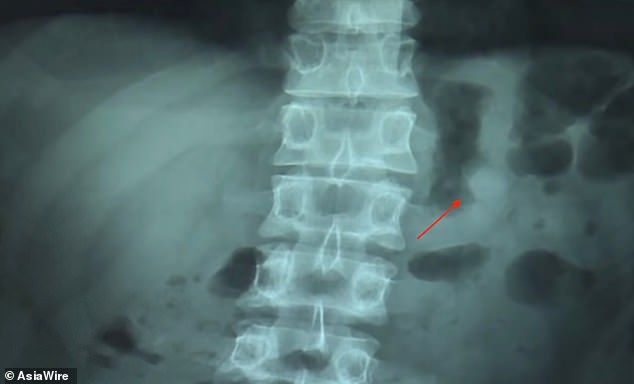

Ben Hsu, bo tak nazywa się mężczyzna, relacjonuje "Daily Mail", że usnął z AirPodami w uszach. Kiedy się obudził, stwierdził brak jednego z nich. – Sprawdziłem pod kocem, rozejrzałem się dookoła, ale nie mogłem go znaleźć – mówi Hsu. – Wtedy zrozumiałem, że dźwięk dochodzi wprost z mojego brzucha – wyjaśnia, jak dokładnie zdiagnozował zaistniały problem.

Pechowiec popędził na izbę przyjęć, gdzie wykonano prześwietlenie. Lekarz potwierdził opinię pacjenta i zalecił środki przeczyszczające, aby pozbyć się ciała obcego.

RTG Bena Hsu / Fot. Asia Wire

Terapia poskutkowała drugiego dnia. Hsu wydalił słuchawkę. Jednak, co zaskakujące, postanowił skorzystać z okazji i wyrazić kilka ciepłych słów na temat firmy Apple i jakości AirPodów. Prawdziwy z niego fan – można by rzec, zwłaszcza mając na uwadze krępujące okoliczności zajścia.

– Słuchawka była nienaruszona, a bateria wciąż miała 41 proc. To było niesamowite – podsumował. Zapewnił też, że teraz jak nigdy jest przekonany o wysokiej jakości produktów Apple'a. I cóż, może coś rzeczywiście jest w kulinarnym powiedzonku, że droga do serca prowadzi przez żołądek ;)